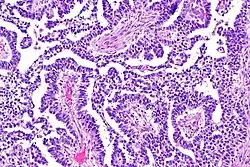

Dysgerminoma

Dysgerminomas are comparable to testicular seminomas and account for approximately 32- 37% of all OGCTs.[1] They are particularly prominent in individuals with dysgenic gonads of 46, XY pure gonadal dysgenesis patients.[1] Based on gross examinations, dysgerminomas are characterized by having a ‘solid, lobulated, tan, flesh-like gross appearance with a smooth surface'.[1] Microscopically, the cellular structure is distinguished by a round-ovoid shape containing ample eosinophilic cytoplasm and an irregularly shaped nuclei.[1] The uniformly positioned cells are separated through the fibrous strands and lymphocytic infiltration is commonly observed.[4]